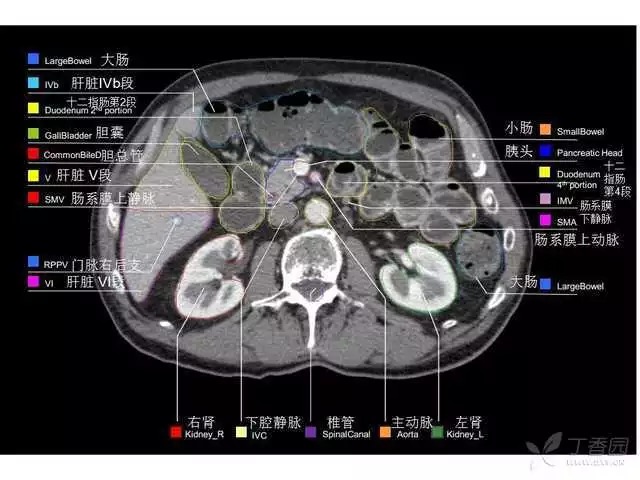

腹部肝脏高清CT断层的图谱

全腹部高清CT图谱,淋巴结彩色图谱,血管解剖图谱大汇总!

肝段,肝内管道的分布规律

美国放射学会ACR官网,对肝脏的区域和节段解剖学概述